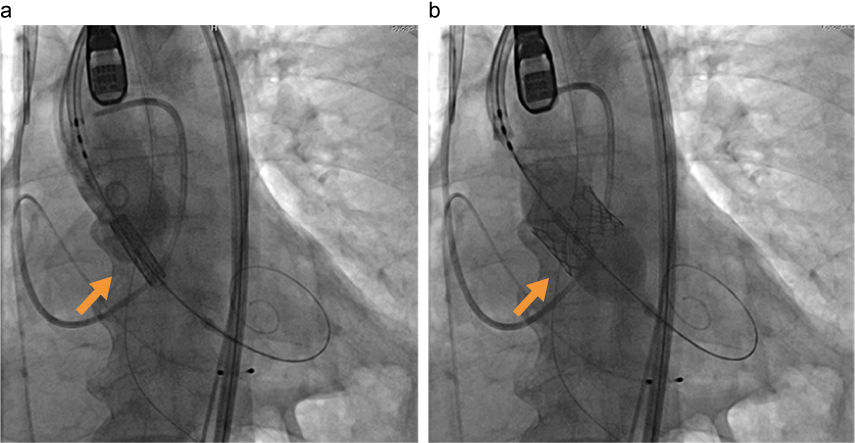

TAVR(経カテーテル的大動脈弁置換術)の実際

出典

img

1: 吉田千佳子先生ご提供